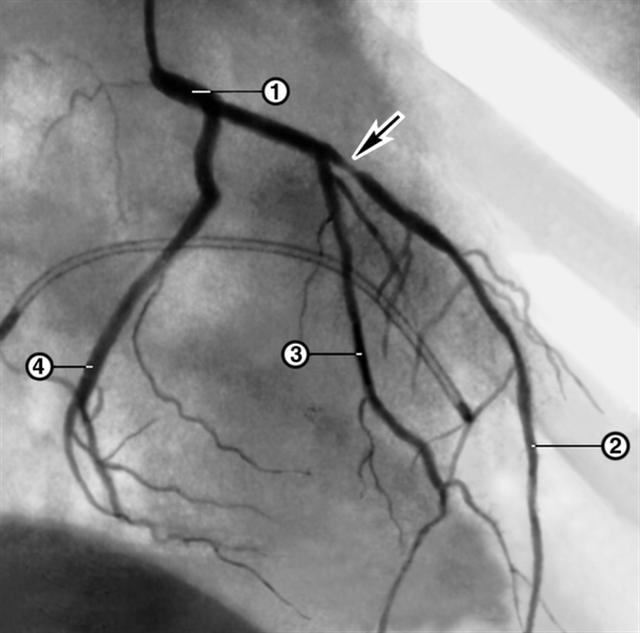

Рис. 2а). Ангиограмма ствола (1) и ветвей левой коронарной артерии (2 — передняя межжелудочковая артерия, 3 — диагональная артерия, 4 — огибающая артерия) больного со стенокардией напряжения: до лечения (стрелкой указано место резко выраженного, примерно на 90%, проксимального стеноза передней межжелудочковой артерии).